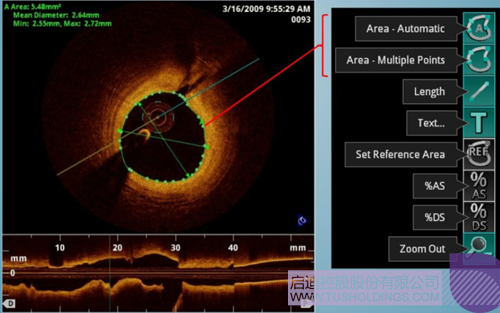

光學(xué)相干斷層成像技術(shù)(OCT)是一種新型影像技術(shù),它利用弱相干光干涉儀的基本原理,檢測生物組織不同深度層面對入射弱相干光的背向反射或幾次散射信號,通過掃描,可得到生物組織二維或三維結(jié)構(gòu)圖像。OCT由于具有極高的分辨率(10 um),可以對內(nèi)膜性質(zhì)和支架結(jié)構(gòu)更加精確地辨別和分析。

在冠脈介入治療迅猛發(fā)展的今天,隨著復(fù)雜病變患者日益增多,血管內(nèi)影像扮演了越來越重要的角色。OCT借助其高分辨率的圖像優(yōu)勢,可以提供更清晰的病變特征和支架植入情況,OCT存在以下優(yōu)勢:可更精確的檢測介入治療后的血管內(nèi)情況,如夾層、支架貼壁不良、組織脫垂等,另外,它在管腔直徑和面積方面的測量精度更高。

血管腔內(nèi)精準(zhǔn)評估